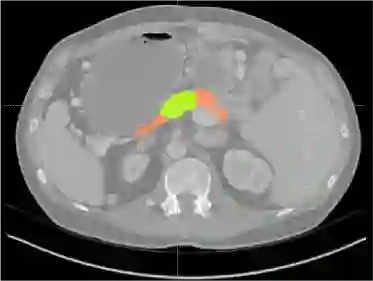

Creating large-scale and well-annotated datasets to train AI algorithms is crucial for automated tumor detection and localization. However, with limited resources, it is challenging to determine the best type of annotations when annotating massive amounts of unlabeled data. To address this issue, we focus on polyps in colonoscopy videos and pancreatic tumors in abdominal CT scans; both applications require significant effort and time for pixel-wise annotation due to the high dimensional nature of the data, involving either temporary or spatial dimensions. In this paper, we develop a new annotation strategy, termed Drag&Drop, which simplifies the annotation process to drag and drop. This annotation strategy is more efficient, particularly for temporal and volumetric imaging, than other types of weak annotations, such as per-pixel, bounding boxes, scribbles, ellipses, and points. Furthermore, to exploit our Drag&Drop annotations, we develop a novel weakly supervised learning method based on the watershed algorithm. Experimental results show that our method achieves better detection and localization performance than alternative weak annotations and, more importantly, achieves similar performance to that trained on detailed per-pixel annotations. Interestingly, we find that, with limited resources, allocating weak annotations from a diverse patient population can foster models more robust to unseen images than allocating per-pixel annotations for a small set of images. In summary, this research proposes an efficient annotation strategy for tumor detection and localization that is less accurate than per-pixel annotations but useful for creating large-scale datasets for screening tumors in various medical modalities.